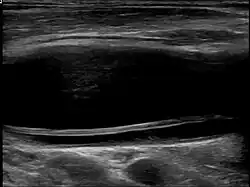

| Diagnostic method | Ultrasound, MRI, MRA, CTA |

Carotid artery dissection can occur spontaneously or be triggered by trauma, including minor injuries, certain medical conditions, or activities that involve neck movement. It is a leading cause of stroke in young and middle-aged adults. The condition is typically diagnosed through imaging studies, such as ultrasound, magnetic resonance imaging (MRI), magnetic resonance angiography (MRA), or computed tomography angiography (CTA), which help visualize the blood vessels and detect abnormalities.